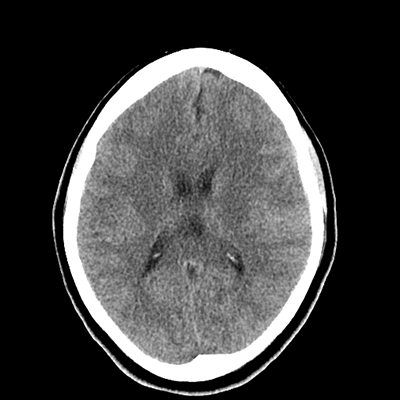

NCHCT

With that in mind, as we look at her neuroimaging, it's subtle, but we can appreciate a faint SAH in the left frontal lobe convexity. Her vessel imaging is unremarkable.